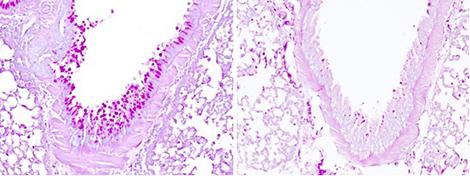

A team of Inserm and CNRS researchers from the Institute of Pharmacology and Structural Biology--or IPBS (CNRS / Université Toulouse III--Paul Sabatier)--have identified a protein that acts like a sensor detecting various allergens in the respiratory tract responsible for asthma attacks. Their study, codirected by Corinne Cayrol and Jean-Philippe Girard, is published in Nature Immunology on 19 March 2018. These scientists' work offers hope for breakthroughs in the treatment of allergic diseases.

The IPBS team has identified a human protein that reacts to many environmental allergens: interleukin-33 (IL-33). When allergens enter the human respiratory tract, they release proteases that hack IL-33 molecules into extremely reactive pieces triggering the chain reactions behind allergy symptoms.

Apparently, the same mechanism is responsible for these reactions after exposure to any of several different allergens. As a matter of fact, IL-33 was shown to detect 14 different allergens tested, which include some present in ambient air (i.e. pollen, house dust mites, and fungal spores) and others associated with occupational asthma (like subtilisin, found in detergents).